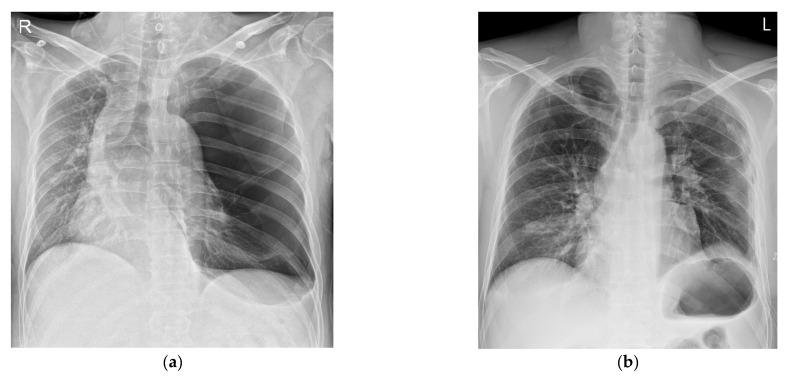

: Giant bullae rupture easily and cause tension pneumothorax, which can cause problems during general anesthesia. However, the hemodynamic instability that can occur due to the mass effect of an unruptured giant bulla should not be overlooked. : A 43-year-old male patient visited the emergency room with an abdominal wound. There was a giant emphysematous bulla in the left lung. Emergency surgery was decided upon because there was active bleeding according to abdominal CT. After tracheal intubation, the patient's blood pressure and pulse rate dramatically decreased. His blood pressure did not recover despite the use of vasopressors and discontinuation of positive pressure ventilation applied to the lungs. Thus, a bullectomy was immediately performed. The patient's blood pressure and pulse rate were normalized after the bullectomy. : If emergency surgery under general anesthesia is required in a patient with a giant emphysematous bulla, it is safe to minimize positive pressure ventilation and remove the giant emphysematous bulla as soon as possible before proceeding with the remainder of the surgery. Tension pneumothorax due to the rupturing of a bulla should be considered first. However, hemodynamic changes might occur due to the mass effect caused by a giant bulla.

: 巨大的肺大疱容易破裂并导致张力性气胸,这可能会在全身麻醉期间引发问题。然而,不应忽视未破裂的巨大肺大疱的肿块效应可能导致的血流动力学不稳定。: 一名 43 岁的男性患者因腹部伤口到急诊就诊。患者左侧肺部有巨大的气肿性肺大疱。根据腹部 CT 检查有活动性出血,决定进行紧急手术。气管插管后,患者的血压和脉搏率急剧下降。尽管使用了血管加压药并停止了对肺部的正压通气,但患者的血压仍未恢复。因此,立即进行了肺大疱切除术。肺大疱切除术后,患者的血压和脉搏率恢复正常。: 如果需要在巨大的气肿性肺大疱患者中进行全身麻醉下的紧急手术,在进行手术的其余部分之前,通过最小化正压通气并尽快切除巨大的气肿性肺大疱,这样做是安全的。首先应考虑因肺大疱破裂导致的张力性气胸。然而,由于巨大的肺大疱引起的肿块效应,可能会发生血流动力学变化。